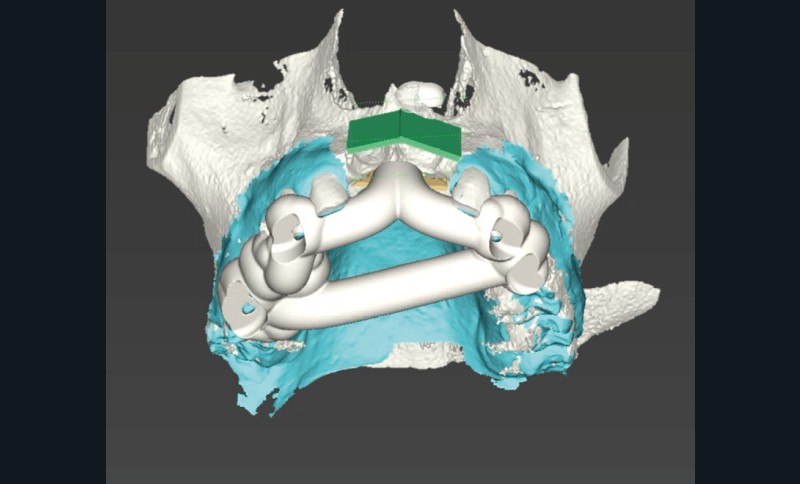

L’avènement des technologies numériques a permis d’améliorer la précision de ces procédures. La planification implantaire 3D, associée à la conception et fabrication assistée par ordinateur (CAD/CAM), permet aujourd’hui de concevoir des guides chirurgicaux spécifiques optimisant et sécurisant le positionnement des blocs osseux. De même, la démocratisation récente des techniques de chirurgie guidée dynamiques par caméra stéréoscopique constitue un outil attractif pour les techniques de reconstruction osseuse. Ainsi, la taille du bloc à prélever sur la zone rétromolaire mandibulaire peut aussi être exactement déterminée en amont de la chirurgie (fig. 1 et 2).

La possibilité de réaliser le prélèvement osseux en bloc avec un guide statique permet d’affiner sensiblement la quantité d’os prélevée en fonction du besoin réel et diminuer la morbidité du geste. En revanche, le positionnement même du guide nécessite l’ouverture d’un lambeau de grande taille.

La chirurgie guidée dynamique permet, quant à elle, de prélever par piezochirurgie (Piezotouch, Mectron) de façon naviguée (fig. 3). Ainsi, le bloc peut être designé en amont sur le logiciel de planification implantaire pour correspondre parfaitement au défaut osseux en présence, et prélevé à l’identique sur la ligne oblique externe (fig. 4 à 8).